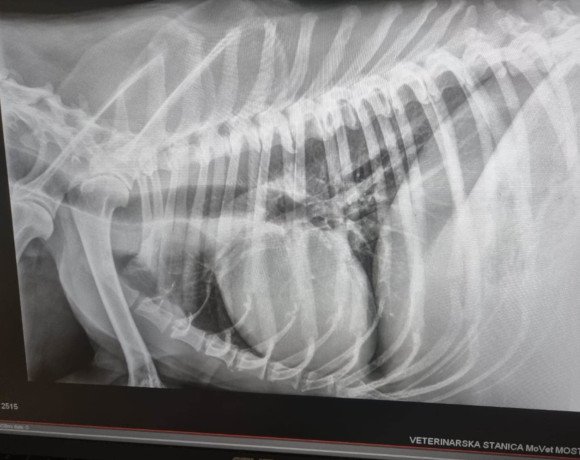

Die Untersuchungen beim Tierarzt haben leider ergeben, dass er einen Milztumor hat und der Krebs bei Dedo bereits so weit fortgeschritten ist, dass eine Operation keinen Sinn mehr ergeben würde. Die Narkose wäre für ihn ein zu großes Risiko, und wir wollen ihm unnötiges Leiden ersparen. Stattdessen haben wir beschlossen, Dedo seine letzten Tage, Wochen oder Monate so angenehm wie möglich zu gestalten. Dedo darf nun bei unserer Tierschützerin vor Ort im Zwinger leben, da er das Leben draußen gewohnt ist und drinnen nicht bleiben möchte. Sie sorgt liebevoll für ihn und kocht ihm sogar seine Mahlzeiten selbst – eine kleine Freude, die ihm in dieser schweren Zeit geblieben ist. Bitte helft uns, Dedo die letzten Momente seines Lebens so schön wie möglich zu machen. Eine Futter- oder Medizinpatenschaft würde uns sehr helfen, damit wir Dedo in seiner letzten Zeit angemessen versorgen können.